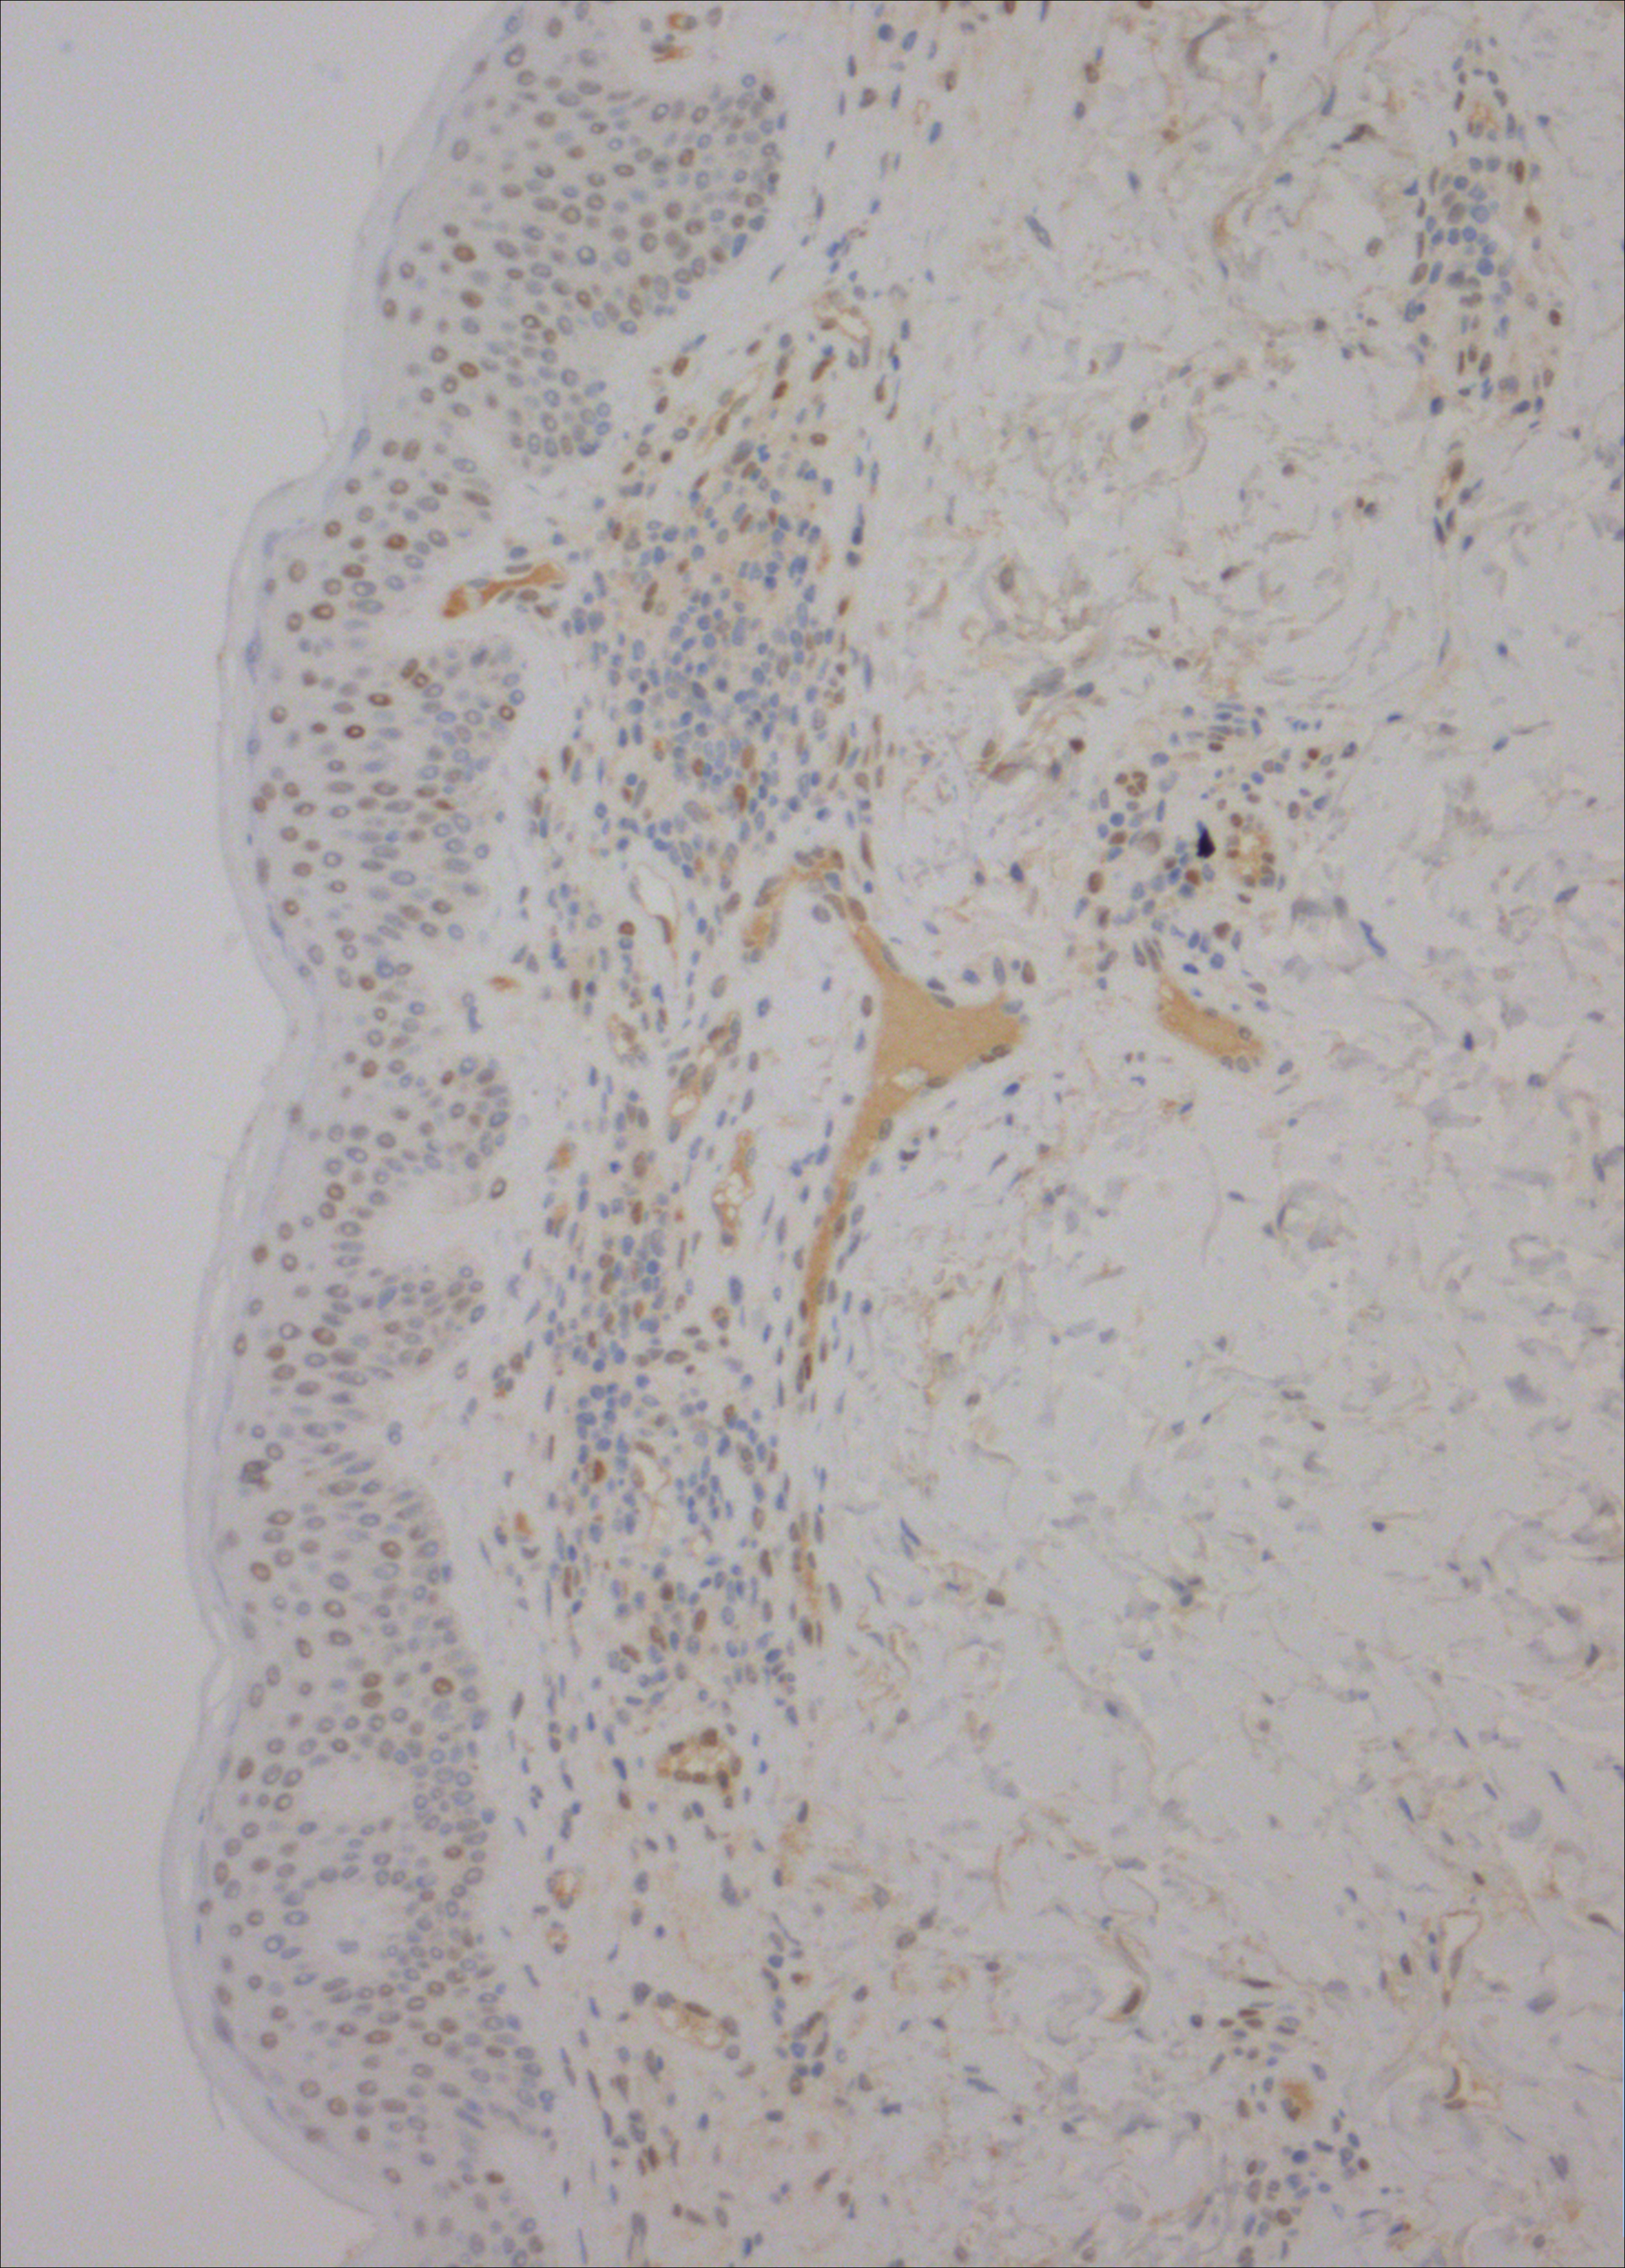

Weak tyrosine-phosphorylated STAT3 staining (brown) in keratinocytes and lymphocytes in skin lesions from cutaneous T-cell lymphoma following aggressive antibiotic treatment, indicating that eradication of Staphylococcus aureus is associated with inhibition of tumor and disease activity. See the article by Lindahl et al on page 1072.

Antibiotics inhibit tumor and disease activity in cutaneous T-cell lymphoma

This paper reports that aggressive antibiotic treatment inhibits disease activity and lymphocyte proliferation in cutaneous T-cell lymphoma (CTCL). The study offers important evidence for a link between bacterial infection, activation of the immune system, and CTCL progression.